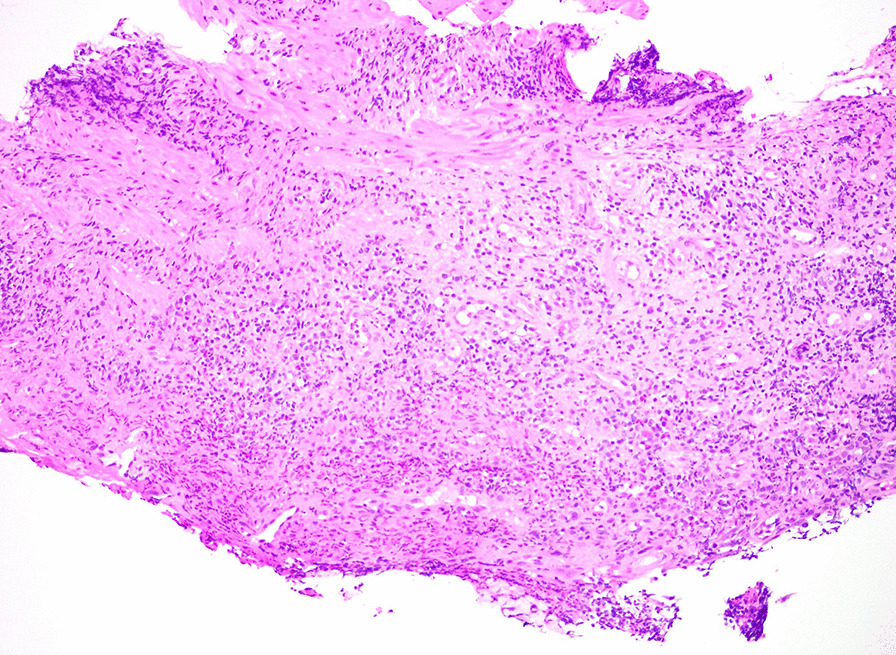

Fig. 2.

Histological image of the distal esophageal biopsy specimen. Hematoxylin and eosin stain of the patient’s distal esophageal mucosal biopsy specimen demonstrating granulation tissue with acute on chronic inflammation. Photograph provided by Dr. Vikram Deshpande (Massachusetts General Hospital)